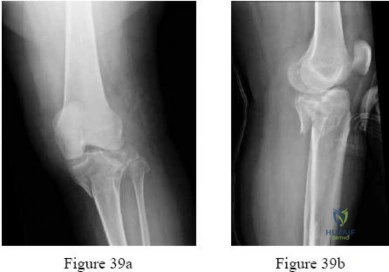

Question 17:

Correct Answer: Type II

Explanation:

The Schatzker classification for tibial plateau fractures is: Type I: split fracture of the lateral plateau (typically younger patients). Type II: split-depression fracture of the lateral plateau (most common, older patients). Type III: pure central depression of the lateral plateau. Type IV: medial plateau fracture. Type V: bicondylar fracture. Type VI: metaphyseal-diaphyseal dissociation. A split-depression lateral plateau fracture is a Type II.

Question 25:

A 55-year-old male sustains a high-energy varus impact to his knee. Radiographs reveal a medial tibial plateau fracture with significant depression and widening. What is the Schatzker classification for this injury, and what is the associated soft tissue injury most commonly seen?

Correct Answer: Schatzker IV; lateral collateral ligament / posterolateral corner injury

Explanation:

A medial tibial plateau fracture represents a Schatzker IV. This is typically a high-energy pattern resulting from severe varus stress, often leading to distraction or avulsion injuries to the lateral-sided structures, including the lateral collateral ligament (LCL) and the posterolateral corner (PLC).